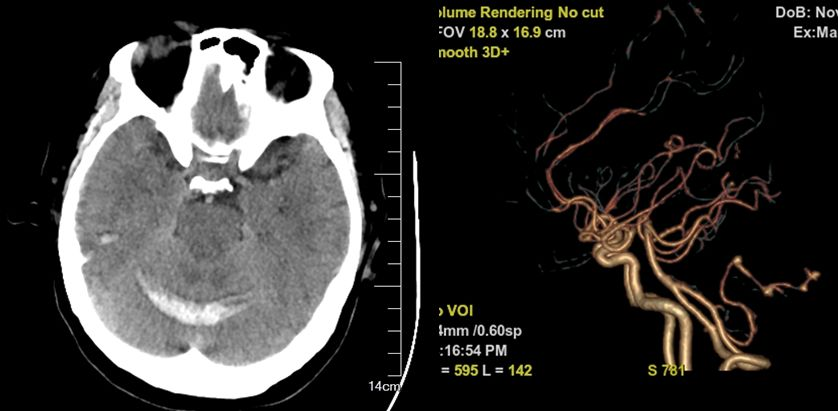

急诊头颅CT+CTA:蛛网膜下腔出血、右侧小脑后下动脉动脉瘤。

图1 术前CT+CTA